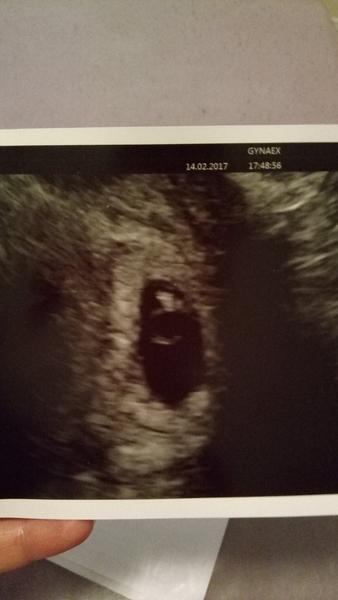

@judit_ka ja som mala ms naposledy 25.12.2016 ja som to najprv pripisovala ms no ale potom sa mi zväčšili prsia a spravili take modré zilky to som nikdy nemala, neviem nic spapat nasilu jem lebo mam žalúdok ako na vode a v utorok som vracala večer.. Neviem, nic take az na tie prsia a to ze mi je naozaj strasne od žalúdka 🤒 A este mi zvykla byt strasna zima a teraz posledne dni veľa spim.. Všetci mi vraveli ze ty si urcite tehotná a ja ze ale kde dokonca priateľ mi vcera rano chytil bruško a povedal ze som tehotná a uz mi to nedalo tak som volala babke nech mi zbehne kúpiť test lebo žijem vo Viedni a šla som ku nej na víkend no a večer bum na mna dve čiarky ❤️❤️❤️ Nemôžem uveriť ze mam v brušku babo